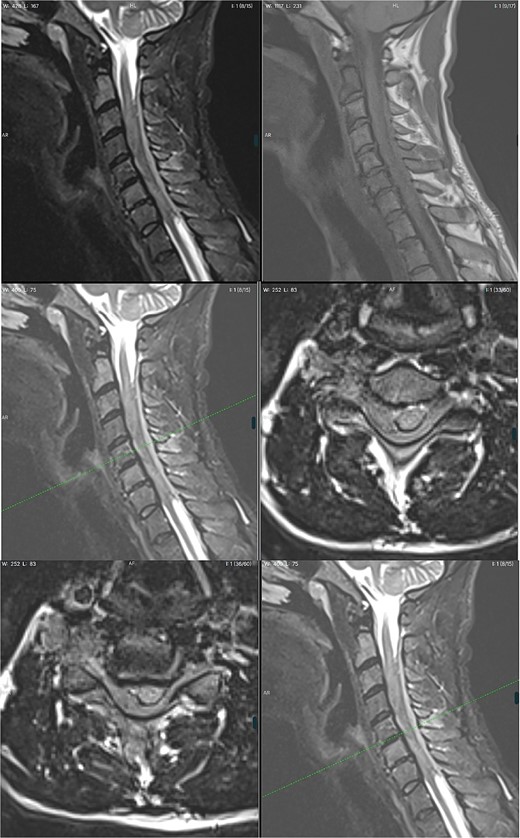

A 42-year-old man was admitted to the emergency department (ED) with progressing tetraplegia. A week earlier the patient had a session of spinal manipulation therapy (SMT), which he underwent due to his previous fall on a ship a few weeks before. During SMT, he heard a loud crack in his neck. The following day he woke up with numbness and weakness in his lower extremities, symptoms slowly progressed and after a week he was affected by tetraparesis and decided to seek help at the ED. The patient was fully conscious with a GCS score of 15. Further neurological examination revealed proximal and distal weakness of 3/5 in the Medical Reaserch Council (MRC) scale in both upper extremities. Greatest severity was noted in hand grip bilaterally, impaired touch sensation in ulnar nerve distribution bilaterally. In the lower limbs, weakness of hip flexors and extensors was graded 3/5 MRC, foot dorsiflexion and plantar flexion of 2/5 MRC. Impaired sense of touch and pain bilaterally from the level of the mid-thighs distally, pain and temperature sensation in the limbs was preserved. Pain and temperature sensation in the lower limbs was preserved. Deep tendon reflexes of the lower extremities were vivid and symmetrical. Moreover, the patient also presented with a bilateral positive Babinski sign. Ataxia could not be assessed due to paresis. Non-contrast Magnetic Resonance Imaging (MRI) visualized a lesion located at C3–C7 causing vertebral cord compression with abolition of the subarachnoid space and edema of soft tissues surrounding spinous processes. Increased signal of the C2 and C6 vertebral bodies in T2-weighted images suggested post-traumatic changes. Features of massive edema of the spinal cord over a section of ⁓10 cm (from the level of the lower part of the C2 body to the upper part of the T1 body), with the elimination of the perimedullary fluid space in this section—features of intracanal tightness were also observed. In the C3–C7 section, an extensive right-sided epidural hematoma was suspected (Fig. 1.). The radiological diagnosis was extensive spinal cord compression by spinal epidural hematoma in the cervical region. The patient was admitted to the Neurosurgery Department and qualified for emergent surgery. A C3–C7 laminectomy was performed. After removing the ligamentum flavum, no sign of hematoma could be noticed. Instead a tumorous mass was found overlaying the thecal sac. Due to dura infiltration a subtotal resection was performed in order to decompress the spinal cord. Samples were sent for post-op histopathological examination. The following day, the patient was extubated as his condition improved. The day after surgery, with the assistance of a physiotherapist, the patient was placed in an upright position and walked with the help of a walking frame. Over the recovery period of 8 days, gradual amelioration of previous neurological symptoms occurred with his overall state being stable. Rehabilitation counseling was ordered in which tetraplegia, flaccid paresis in the upper limbs, more severe distally, and spastic paresis in the lower limbs were still described. No sensory disorders were detected. Generalized muscle atrophy was noticed. After pathomorphological evaluation the diagnosis of diffuse large B-cell lymphoma (DLBCL) was made. The patient was discharged home to wait for further oncological treatment. On the 17th day after discharge, the patient returned to the ED due to progression of limb paresis. He was then referred to the Oncology and Radiotherapy Department, where radical radiotherapy was administered. In the next few days the patient presented with fever and increased inflammatory parameters were noticed. Chest X-ray revealed bilateral pneumonia with fluid in the left pleural cavity resulting in pleural drainage. Due to the lack of improvement in the patient's condition after 40 days of hospitalization, bronchofiberoscopy was performed. During the procedure, bleeding from the respiratory tract occurred further complicated by cardiac arrest in the asystole mechanism. Successful cardiopulmonary resuscitation was performed. The patient was transferred to the Anaesthesiology and Intensive Care Department. During the next 2 days, the patient remained sedated and intubated, with no apparent improvement. With symptoms of multiple organ dysfunction, the patient suffered a second cardiac arrest. Due to exhaustion of further treatment options, resuscitation activities were not performed and the patient died.